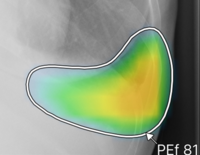

(2)ヒートマップ/輪郭表示機能

異常所見の存在可能性(確信度)を,青から赤へのグラデーションで示すヒートマップ表示について,多くの利用者から好評を得ている。一方,モノクロモニタを利用する一部の読影環境では,淡いヒートマップが確認しにくいという課題があった。新バージョンでは,異常所見の疑われる領域の表示方法として,「ヒートマップ表示」「輪郭表示」「ヒートマップと輪郭の併用表示」の3つの表示パターンが選択可能になった。これにより,各施設の運用環境に応じた最適な表示方法を利用できる。

ヒートマップ表示 |

輪郭表示 |

ヒートマップと輪郭の併用表示 |